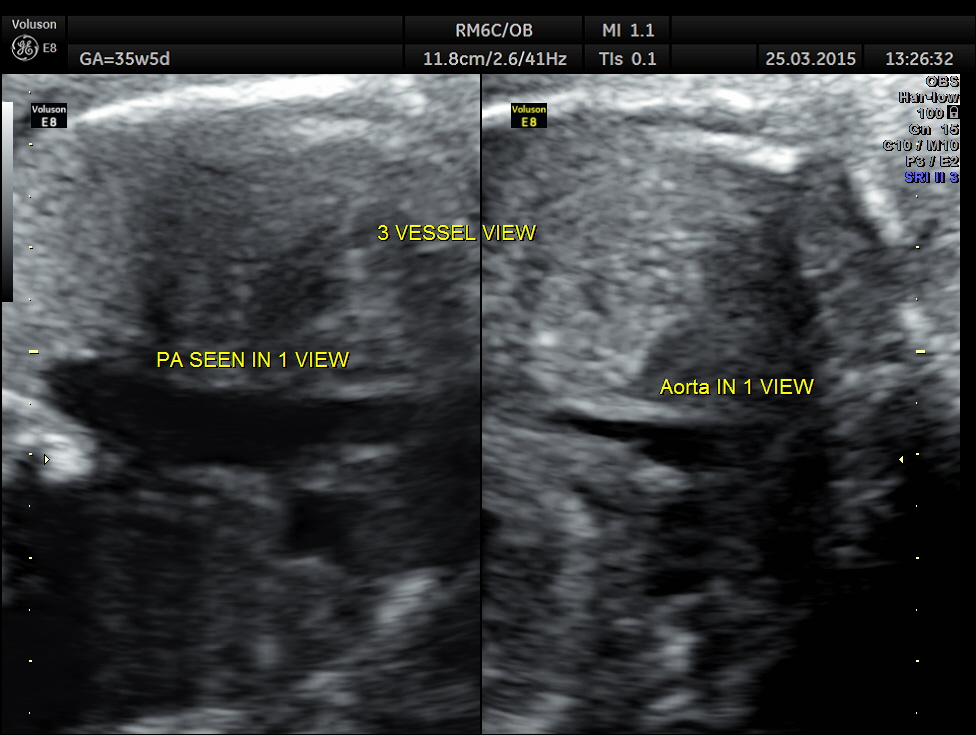

In the three vessel view , single big vessel is seen in a plane.

3 vessel view shows only a single vessel in a given plane.

3 Vessel trachea view show only one great vessel in a given plane.